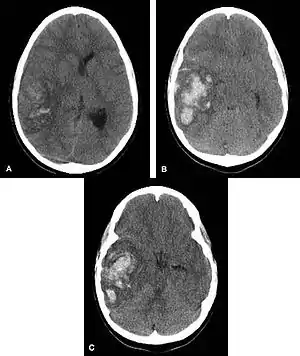

Hemorrhagic neoplasms are more complex, heterogeneous bleeds often with associated edema. These hemorrhages are related to tumor necrosis, vascular invasion and neovascularity. Glioblastomas are the most common primary malignancies to hemorrhage while thyroid, renal cell carcinoma, melanoma, and lung cancer are the most common causes of hemorrhage from metastatic disease.